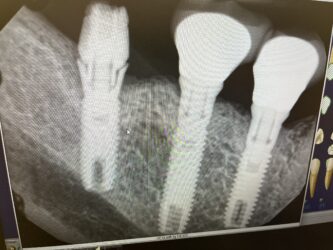

Pt has had #29-#31 implant placed 30 years ago, #30 and #29 in good functional condition. #31 hasnt had functional crown for last 10 years. has kept ” failling off”

Fractured/ flowered implant collar? abutment is loose, looks like possible fractured screw.

Is removing the only reccomended treatment for #31 implant for this case at this stage?